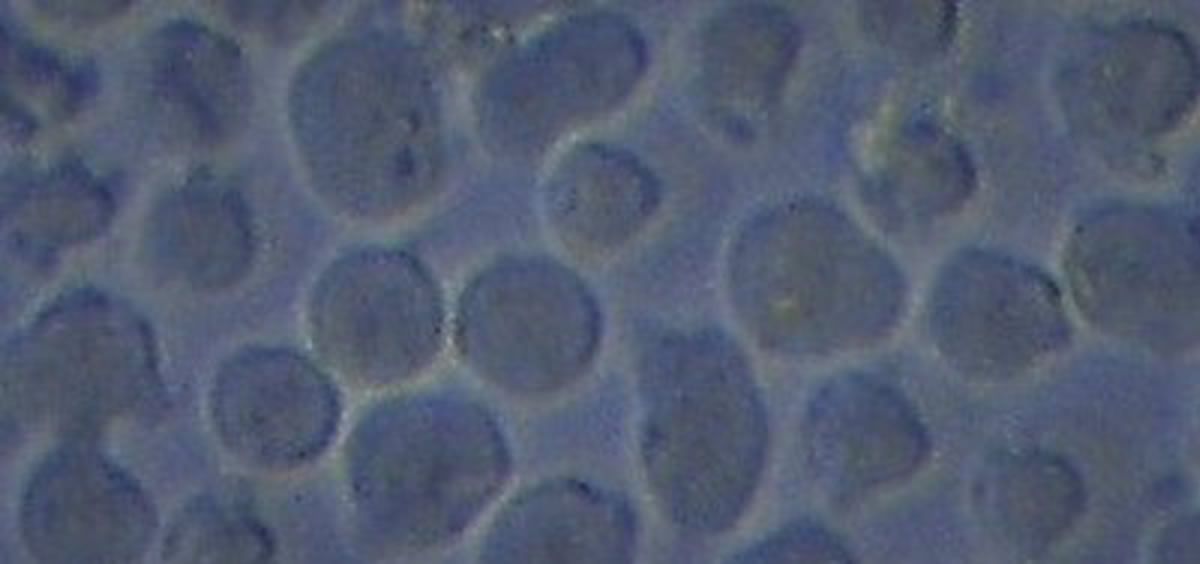

Desde hace pocos, años existe una alternativa para estos casos: la terapia celular CAR-T, que recoge los linfocitos T de estos pacientes, los modifica mediante ingeniería genética en el laboratorio y los administra nuevamente al paciente, para que ataquen de forma más efectiva al cáncer. Esta estrategia ha significado una revolución en el campo del tratamiento de las enfermedades hematológicas malignas.

Estos investigadores decidieron mirar en detalle las caracteristicas moleculares de más de 100 muestras de células CAR-T proporcionadas a pacientes con leucemias y linfomas, y descubrieron que existía un perfil de regulación genética (epigenoma) que estaba asociado a la ausencia de reaparición de la enfermedad y a una mejor supervivencia global de estas personas.